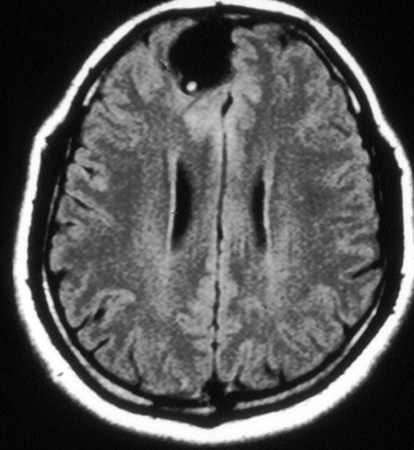

Calcified stage - neurocysticercosis: MRI scan of multiple calcified lesions in a patient with neurocysticercosis

From the personal collections of Dr Christina Coyle and Dr Maheen Saeed; used with permission